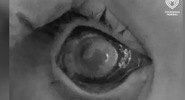

В Москве двое 15-летних школьников решили повторить эксперимент из интернета и едва не остались без зрения.

Парни смешали бытовую химию у себя дома. Случилась неконтролируемая реакция, последовал взрыв. Смесь попала на лицо подростков, они получили серьезные ожоги глаз.

Пострадавших экстренно госпитализировали. Врачи Морозовской детской городской клинической больницы успешно провели серию операций и комплексную терапию, сообщили в Департаменте здравоохранения столицы,

Одному ребенку удалось полностью восстановить зрение, другому – на 60%, хотя при подобных повреждениях существовал высокий риск полной слепоты.